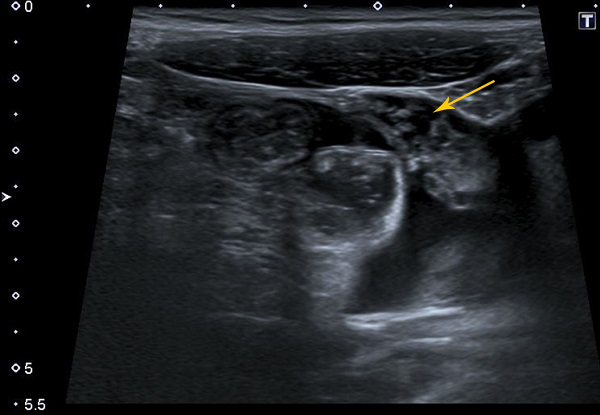

Adolescente de 15 años de edad que ingresó en planta de hospitalización por dolor abdominal localizado en ambas fosas iliacas de una semana de evolución. Asociaba deposiciones pastosas, en número de 4-5 al día. Afebril, sin vómitos. A su llegada a urgencias presentaba dolor abdominal difuso, más intenso en fosa iliaca derecha. Blumberg dudoso y Murphy negativo. Hallazgos analíticos anodinos, salvo proteína C reactiva de 6,46 mg/dl y procalcitonina de 0,21 ng/ml. Se realizó interconsulta a Cirugía Pediátrica y a Ginecología y se descartó patología quirúrgica urgente. Se solicitó ecografía abdominal (Fig. 1), donde se objetivaron signos de enteritis inflamatoria/infecciosa con afectación del omento mayor. Se ingresó a la paciente con analgesia intravenosa para manejo del dolor, seguimiento evolutivo y filiación del origen del engrosamiento omental. Prueba de la tuberculina negativa. En el coprocultivo se documentó una infección por C. jejuni.

| Figura 1. Torta omental (omental cake). Ecografía abdominal, en la que se evidencia un notable engrosamiento edematoso del omento mayor, localizado en fosa iliaca izquierda |

La ecografía es una buena alternativa a la TC como prueba de inicio, especialmente en niños, en los que las causas neoplásicas de omental cake son raras. Permite evaluar de forma general la afectación peritoneal y describir el patrón (difuso o nodular) sin necesidad de radiación2. En nuestro caso, fue la prueba de imagen diagnóstica (Fig. 1), junto con el coprocultivo, que permitió identificar la infección por C. jejuni y filiar así la causa.